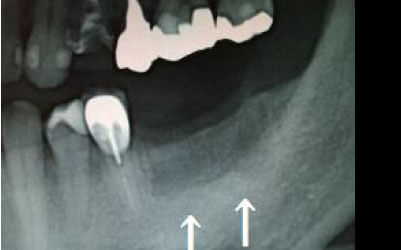

骨が薄い場合、そのままインプラントを行うのはお勧めできません。

ただし、事前に骨を増やす治療を行ったり、インプラントと同時に骨を増やす治療を行えば、インプラントは可能です。

特に、抜けたのが前歯ですとなおさら気になりますよね。 今回のご質問ですが、抜けた部分の骨が薄いなどの理由で「インプラントはできない」と言われた可能性があります。

前歯はもともと骨が薄く、歯が抜けると時間の経過とともにさらに骨が痩せてきてしまうので、インプラント治療の難易度が高い場所です。 ただ結論からお話すると、インプラント治療は可能です。

なぜなら、もし仮に骨が薄くても、骨の治療によって厚みが増せば、安全にインプラント治療が行えるからです。

なお、前歯のインプラント治療をご希望の方には、注意していただきたい点が4つほどあります。 1)インプラント治療を行う前に、骨の治療が必要かもしれません。

2)骨の治療から始めると、その分、治療期間が長くなります。

3)骨の治療は、通常のインプラント治療よりも難易度が高いため、経験の豊富な先生やインプラント認定医のいる歯科医院で治療を受けることをお勧めします。

4)骨の状況をしっかり把握するためにも、CT撮影が必須となります。 また、インプラント治療においては、周囲の歯の状況や咬み合わせの問題などもしっかりと考えて治療するのがとても大切です。